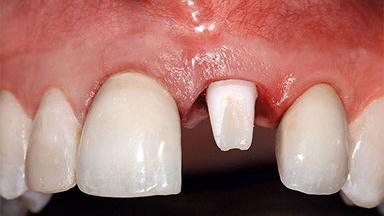

Replacement of a Missing Upper Left Central Incisor: Late Placement of an RC Bone Level Implant, CAD/CAM Zirconia Abutment

Eduardo R Lorenzana, Jason R Gillespie

A healthy 37-year-old female patient was referred for a consultation on the replacement of missing tooth 21 with an implant-supported restoration. She stated that several years previously the tooth had been traumatically avulsed following a motor vehicle accident. The tooth was replaced with a three-unit fixed partial denture (FPD) immediately afterwards. Over time, she became disillusioned with the FPD and looked for a different option, including orthodontic therapy. She presented still in her orthodontic appliances, with the pontic sectioned free from the FPD but attached to the archwire. Her orthodontist felt that orthodontic treatment had been successfully completed, but nevertheless referred her before removing the appliances in case adjustments were necessary.

Bone Volume Deficient horizontally, allowing simultaneous augumentation

Soft Tissue Contour and Volume Slightly compromised